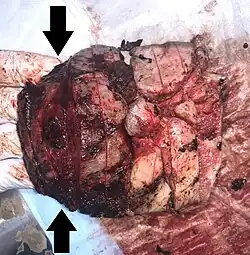

Gross pathology of severe intervillositis, with dark red and soggy tissue. | |